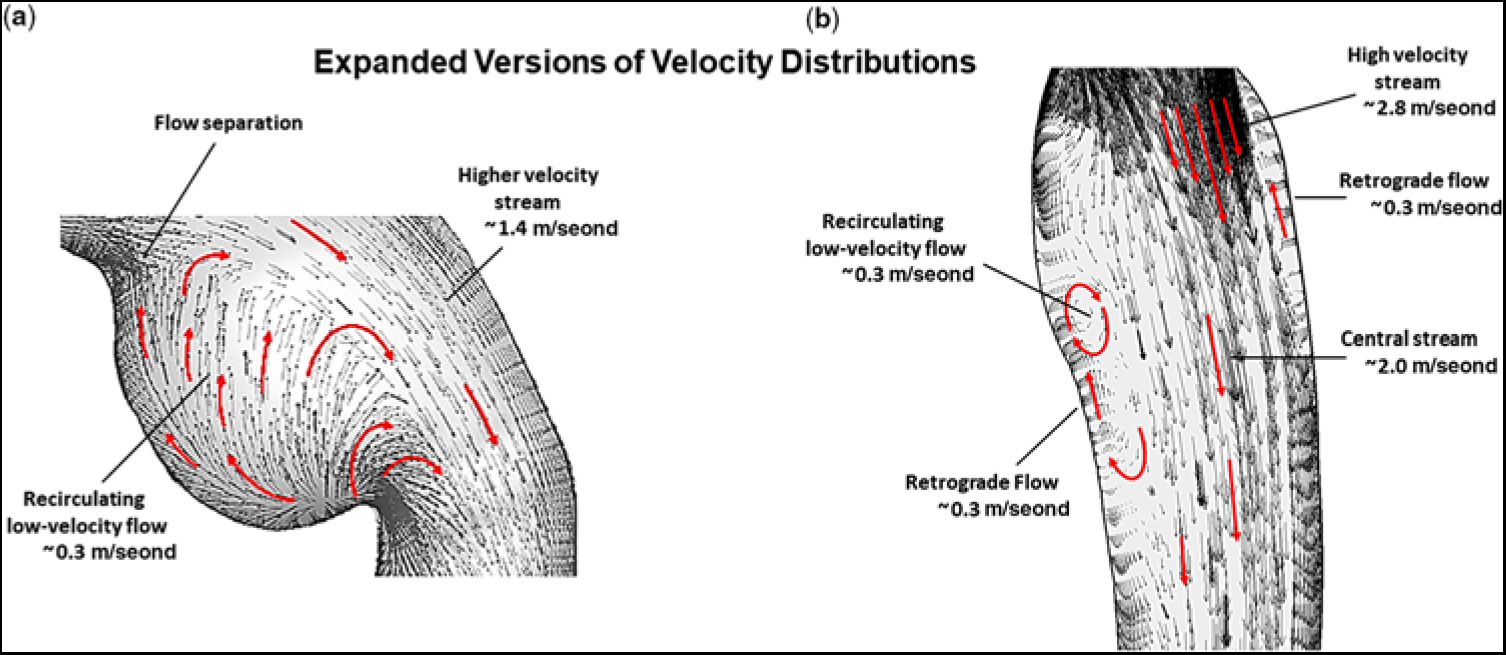

Figure 4a shows an expanded version of the ampulla which contained the low-velocity re-circulating flow. Likewise, Figure 4b shows an expanded version of the thoracic descending aorta beyond the obstruction. The velocity profile that became skewed towards the lateral wall, as the high-velocity (∼2.8 m/second) stream exited the isthmus, is designated by the group of longer straight red arrows. Moreover, as the high-velocity (∼2.0 m/second) central stream advanced along the descending aorta, it created the elongated zone containing low-velocity (∼0.3 m/second) re-circulating (retrograde) flow near the medial wall, and to a lesser extent at the lateral wall, thereby forming zones of sluggish flow, that would be highly favourable for platelet aggregation and thrombus formation. Again, the small black and larger red arrows signify direction of flow.

Figure 4. (a) Expanded version showing the magnitude of flow velocity, in m/second, for (a) the region of the ampulla/isthmus and (b) the thoracic descending aorta, for the portion of the computational domain of primary interest, at peak systole, and prior to stent implantation. The small black and larger red arrows denote direction of flow. In this figure, representative values of flow velocity are shown with the units (m/second).